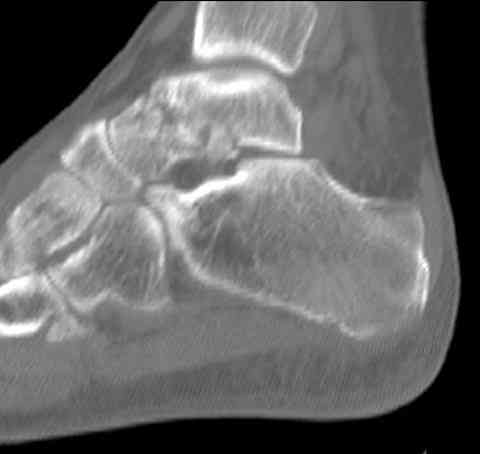

Для оценки состояния нужны дополнительные исследования, например Canale или Broden ренгенограммы и Компьютерная томография.

На ренгенограмме не уловил многоскольчатость тарана, чтобы доказать, конечно, можно было исследовать на КТ, потом КТ дает ориентацию фрагментов.

Два фрагмента суставной поверхности тарана можно восстановить боковой компрессией шурупами и дополнительно костная пластика.

(кстати, на нашем случае была применена костная пластика-allograft crouton для заполнения дефектов)